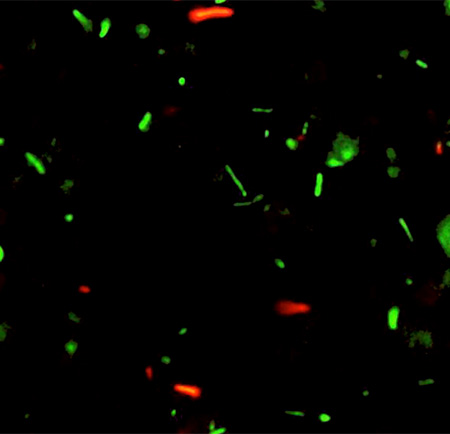

To learn how Salmonellae find their way in the intestine, the researchers observed the movement of S. Typhimurium bacteria (a strain of Salmonella) and compared it to that of a harmless strain of Escherichia coli (E. coli) bacteria.

The study also showed that E. coli and Salmonella respond differently to bioelectric fields. They have opposite responses to the same electric cue. While E. coli clustered next to the villi, Salmonella gathered to FAE.

- Watch Video of E.coli and Salmonella migrating in response to an electric field